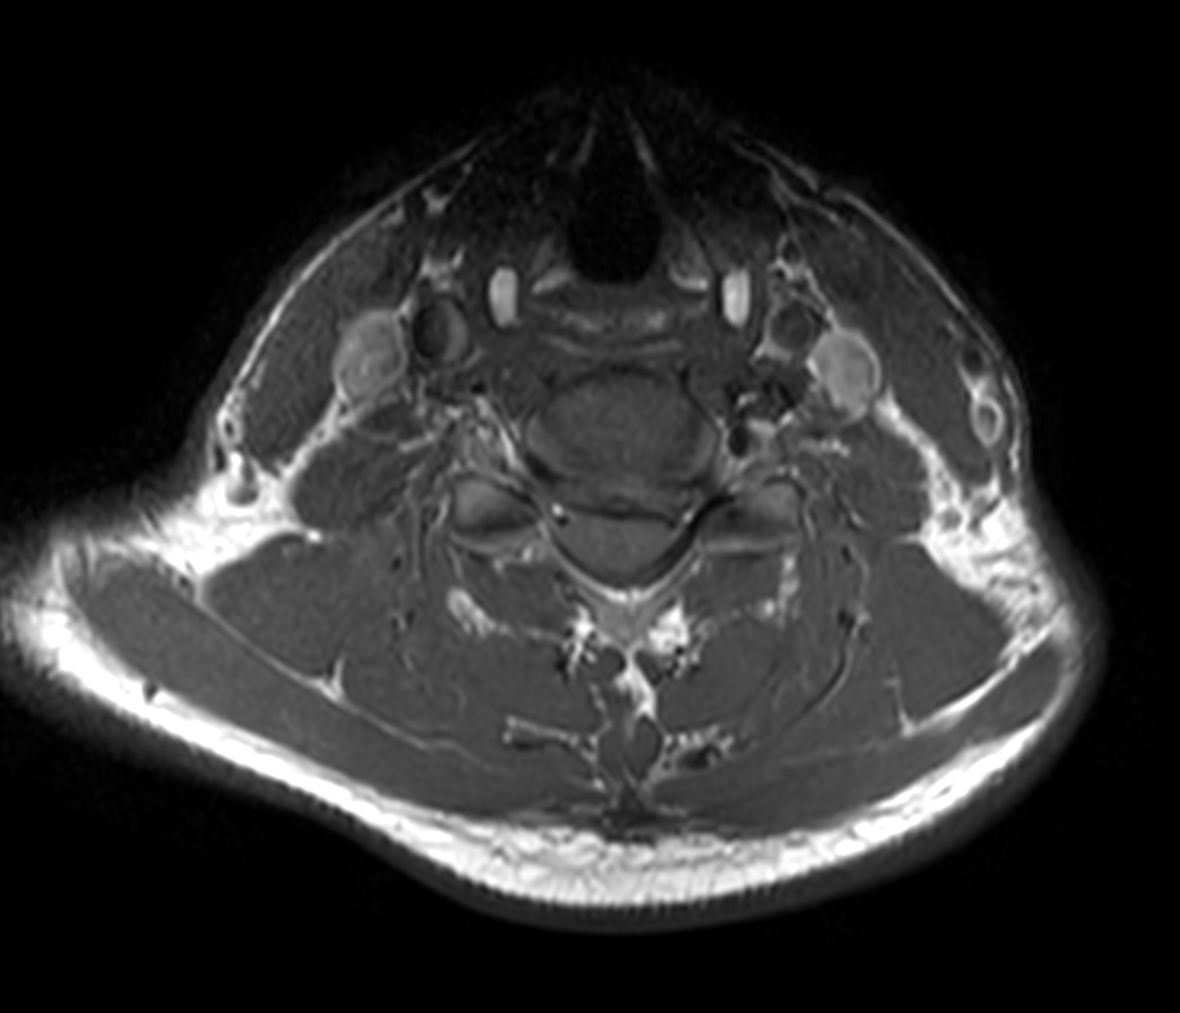

Axial T2w TSE

Axial T2w TSE - Compressed SENSE